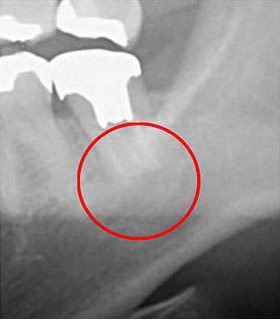

下の画像をご覧ください。

この画像は同じ部位をCT(左)とレントゲン(右)で撮影したものになります。

「右の画像」ですが、丸を付けた部分に黒い影がないと思います。

実は、黒い影は問題が発生している部位です。

つまり、レントゲンだけで診断した場合は、「問題ない」と判断してしまうため治療は行われません。そうなると、この歯は徐々に悪化し、最終的には抜歯の運命をたどっていたでしょう。

このようなことを回避するため、当院ではCT撮影を実施しています。